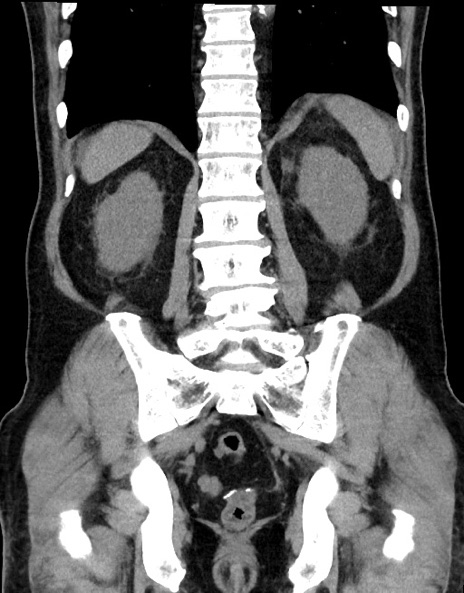

症例15(冠状断像)

【症例】70歳代男性

【主訴】腹痛

【現病歴】今朝から腹痛あり。全体的に痛い。特に左上の方。排ガスが今日はない。冷や汗が出る。

【既往歴】直腸癌術後

【身体所見】左側腹部〜上腹部に圧痛あり。腹膜刺激症状明らかなではない。軽度反跳痛。左下腹部に術後瘢痕あり。

【データ】WBC 7700、CRP 0.02